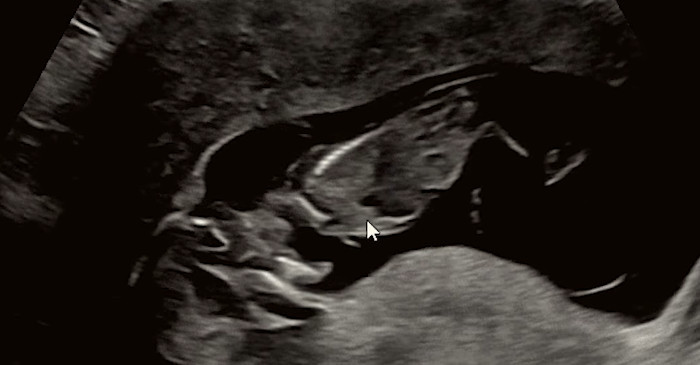

강은비는 영상을 통해 지난 3일 태아를 떠나보냈다고 밝혔다. 그는 임신 경과 중 정기 검진에서 모든 수치가 정상이라는 설명을 들었지만, 이후 양수가 감소했다는 소견을 받았다고 설명했다. 검사 과정에서 양수 누출 가능성이 제기되면서 상급병원으로 이송됐으며, 입원 후 이틀 만에 양수 수치가 0이라는 진단을 받았다고 전했다.

조기양막파열은 출산 진통이 시작되기 전에 양막이 먼저 파열돼 양수가 흘러나오는 상태를 말한다. 일반적으로 양막은 태아를 외부 충격과 세균으로부터 보호하고, 체온과 환경을 일정하게 유지하는 역할을 한다. 이 양막이 예정된 시기보다 빨리 파열되면 감염 위험이 급격히 높아지고, 태아에게 필요한 양수가 줄어들면서 여러 합병증 가능성이 커진다.

특히 임신 37주 이전에 발생하는 경우를 ‘조기 조기양막파열’로 분류하는데, 이 시기에는 태아의 폐와 장기 성숙이 충분하지 않은 경우가 많아 의료진의 판단이 매우 중요해진다. 양수가 지속적으로 빠져나가면 태아의 폐 발달이 제한될 수 있고, 탯줄 압박이나 자궁 내 감염으로 이어질 위험도 있다.

강은비는 해당 병원에서 태아가 가로로 누운 상태로 태반에 밀착돼 있었으며, 폐 발달이 더 이상 어려운 상황이라는 설명을 들었다고 전했다. 의료진은 태아가 매우 제한된 공간에서 버티고 있는 상태라고 판단했다.